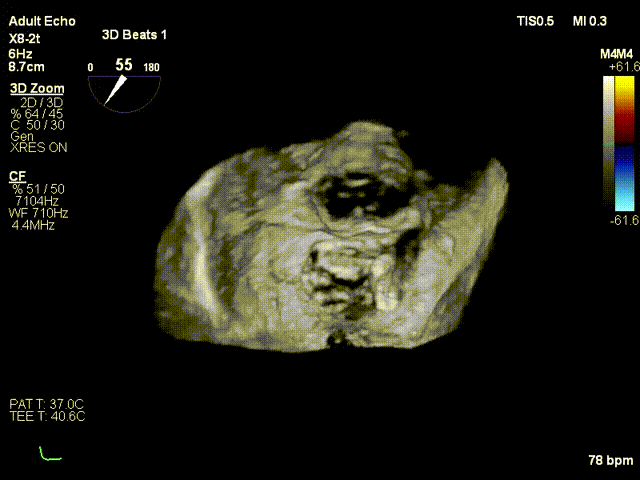

术前3D

术前3D彩色

二尖瓣交界联合彩色

前后瓣叶均可见栓系

反流主要来源于2区累及1、3区